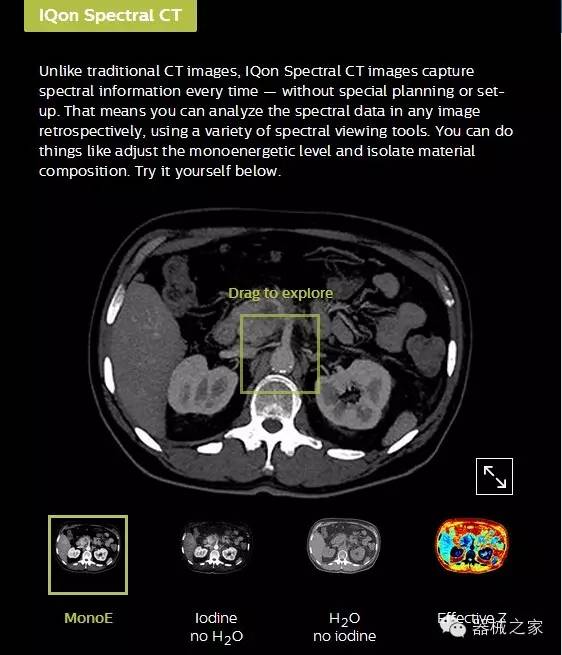

IQon光譜CT能夠按照需求提供光譜量化和工具,并能通過簡單工作流程、在低劑量下對(duì)結(jié)構(gòu)進(jìn)行定性分析

IQon光譜CT -- 是業(yè)界首臺(tái)以探測(cè)器為成像基礎(chǔ)的光譜CT,它可以在單次常規(guī)掃描下獲得傳統(tǒng)解剖影像及光譜功能影像。不僅可以提供精準(zhǔn)的診斷信息,還可簡化工作流程、在低劑量下完成定量與定性分析。